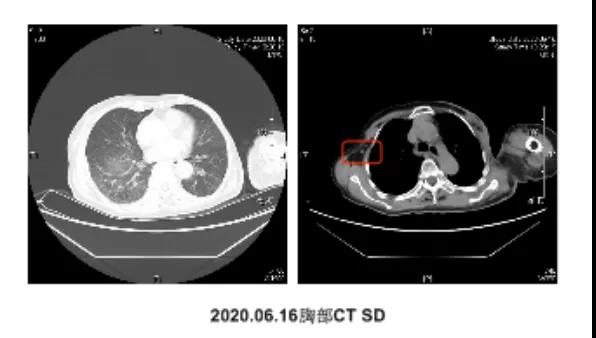

●由于住院患者使用CDK4/6药物渠道不畅通,2020-04-12至06-18更换为“依西美坦25mgQd+氟维司群500mg”联合“阿帕替尼0.25gQd”方案治疗3周期。

第二次化疗:

2020-07,患者左侧胸壁结节增多伴红肿、左上肢红肿伴皮温增高。CT扫描:病灶较前相仿,癌性淋巴管炎较前加重。CA153 28.25U/ml ↑,确定内分泌抗肿瘤治疗效果已经不佳,再次更换为化疗,于2020-07-17、08-10以“吉西他滨1.2gd1、8+卡培他滨1.5g Bid”方案化疗了2个周期,并予以止痛等对症处理。目前,患者左侧胸壁皮肤淡红色疤痕组织,无结节,左上肢肿胀明显好转。病情再次被控制,抗肿瘤化疗正在按计划进行当中。